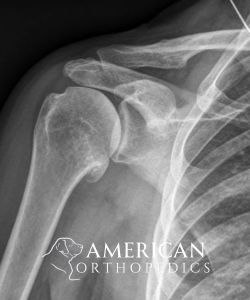

Reverse Total Shoulder for Rotator Cuff Arthropathy

Patient of Dr. Ratner.

Before